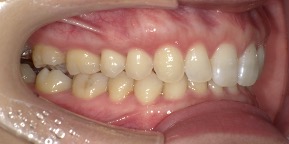

29歳女性のビフォーアフター

| 診断 | 叢生(デコボコがある状態)、過蓋咬合 |

| 治療方針 | インビザラインシステムにて主にIPR(歯と歯の間をわずかに削合してスペースを獲得する方法)を組み込んだ動的矯正治療を行い、叢生を改善後、保定を行う。臼歯部の咬合関係はプランの関係上維持して叢生と前歯部の咬合改善を目指した。 |

| 治療費 ※ | 60万4千円(診断、型取り、PMTC、保定装置を含む料金) |

| 治療期間 | 1年5か月 |

| リスク | 1日20時間以上マウスピースを使用できない場合、歯が動かない可能性がある。装着時や食事時に痛みを伴う。歯肉退縮や虫歯になるおそれがある。また、指導通りに装着できていない場合や適切なブラッシングが出来ていないとそのリスクが高くなる。歯根が短くなることがある。ごくまれに歯の神経が損傷してしまうことがある。過去にぶつけたり深い虫歯治療をしたことがあるとそのリスクはやや高くなる。矯正後には保定装置が必要。適切な使用ができない場合、後戻りの原因となる。将来的に歯並びが動いて再矯正が必要な場合がある。親知らずが正常に生えていない場合、その可能性がやや高くなる。 |